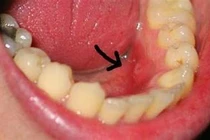

Khi có vấn đề trong cơ thể, hạch có thể sưng to bất thường, đó là một tín hiệu cần chú ý. Không chỉ viêm nhiễm thông thường, hạch còn biểu hiện nhiều bệnh.